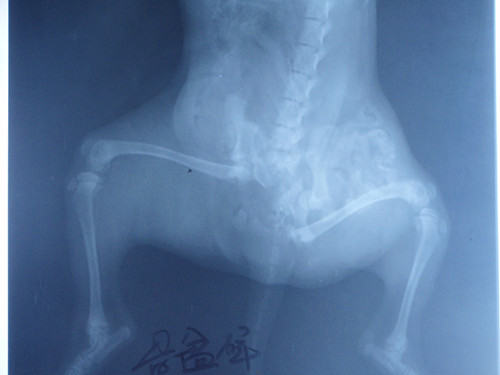

这是一例被碾压的骨盆粉碎性骨折的流浪犬,到医院已经奄奄一息,检查过程中发现腹腔脏器受到严重损害,极度贫血,呼吸困难,结膜苍白,腹部膨大,体温已经检测不到,血压极低,抢救过程中死亡。

骨盆粉碎性骨折的流浪犬